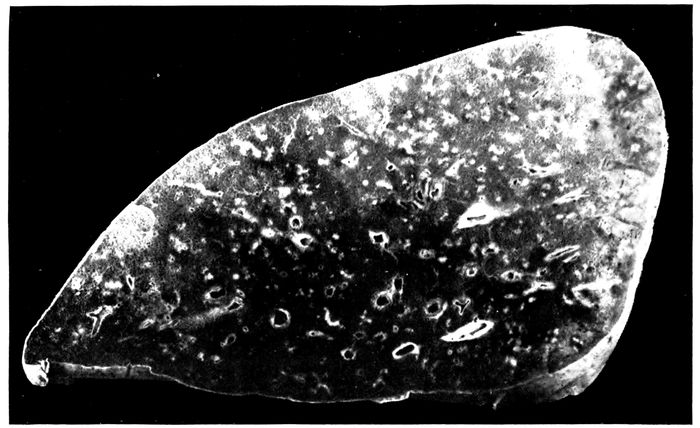

| 2. | Acute bronchopneumonia with nodules of peribronchiolar consolidation and purulent bronchitis | 167 |

| 3. | Acute bronchopneumonia with peribronchiolar consolidation | 169 |

| 4. | Acute bronchopneumonia with peribronchiolar consolidation | 170 |

| 5. | Bronchopneumonia with hemorrhagic peribronchiolar consolidation | 174 |